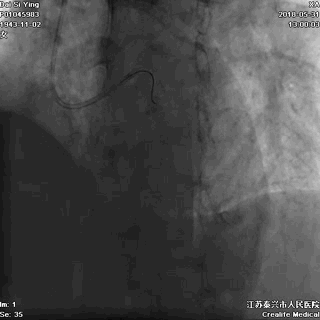

一名许姓的女子,44岁,胸痛3小时后来医院看病,坚持挂门诊,在门诊三楼候诊时,突发恶性心律失常(室颤)。

医护人员马上抢救,电击复律,但她最终还是没挺过来。事后证实,她患的是急性前壁心肌梗死。

上:急性心梗;下:室颤发作

记住:心梗等不起,务必看急诊!大点的医院,急诊科都有急性胸痛的快速急救绿色通道。尤其是设立了胸痛中心的医院,往往要求10分钟内完成首份心电图检查,20分钟内完成心梗三项的检测,30分钟内完成CT检查。绿色通道,才能帮你争分夺秒!